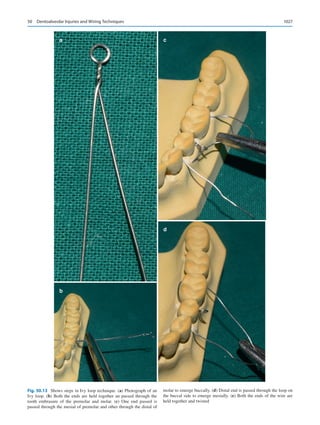

diseases and conditions that are the mainstay to our profes-

sion will alter significantly in the future. Laboratories in

Boston are very close to creating a template stem cells con-

struct that will replace dental implants with naturally grown

teeth. A dental caries vaccine is pending worldwide use.

How will these fundamental changes alter the practice of

our specialty in the future?

Super specialization within the specialty is bound to hap-

pen. Attendees of the annual sessions of the British

Association of Oral and Maxillofacial Surgeons will be